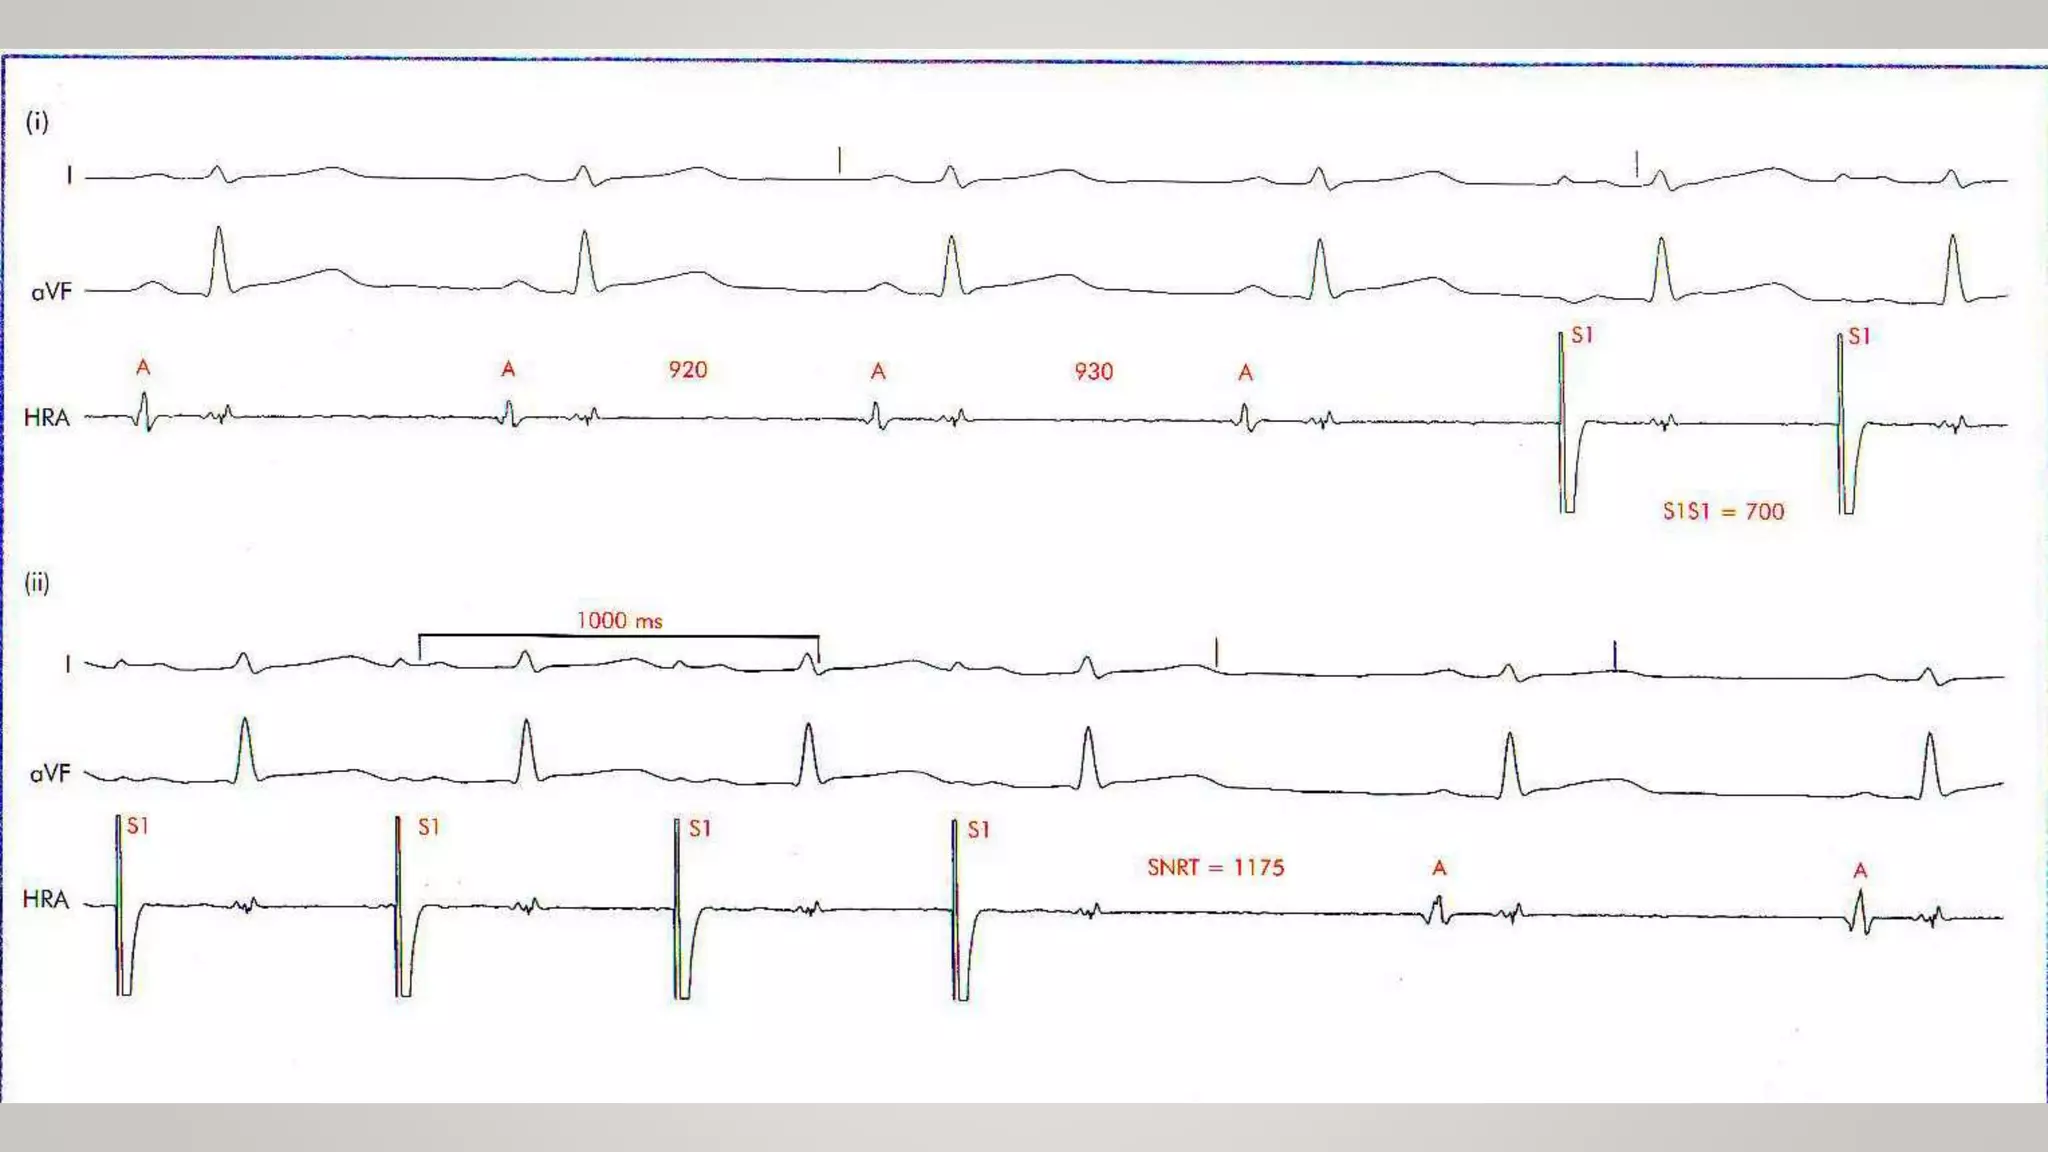

• SN recovery time (SNRT) : Interval from last paced complex to spontaneous complex.

• The corrected SNRT (CSNRT) = SNRT – Sinus CL

Test of SNfunction • SN recovery time (SNRT) : Interval from last paced complex to spontaneous complex. • The corrected SNRT (CSNRT) = SNRT – Sinus CL • Used to detect intrinsic function of the sinus node